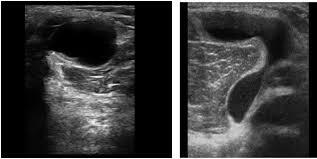

УЗИ - самый доступный и безопасный метод, саму кисту прекрасно видно.

Иногда в полости кисты можно найти какие-нибудь образования, которые мигрировали из полости сустава (кальцинаты, костные тела, хрящевые тела, костно-хрящевые).